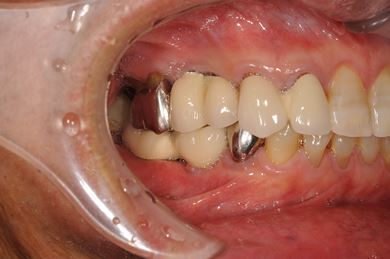

| 性別/年齢 | 男性 / 58歳 | ||||||||||||||||||||||||||||||||

| 主訴 | ブリッジがだめになったため、現在は部分入れ歯を使用しているが、インプラント治療を検討している。 | ||||||||||||||||||||||||||||||||

| 治療方針 | 左上奥の欠損部分をインプラント治療にて、機能的・審美的回復を行う。 | ||||||||||||||||||||||||||||||||

| 治療内容 | インプラント3本(GBR)、ハイブリッドセラミッククラウン3本 | ||||||||||||||||||||||||||||||||

| 総治療費 | 791,520円 | ||||||||||||||||||||||||||||||||

| 治療期間 | 10ヶ月 |